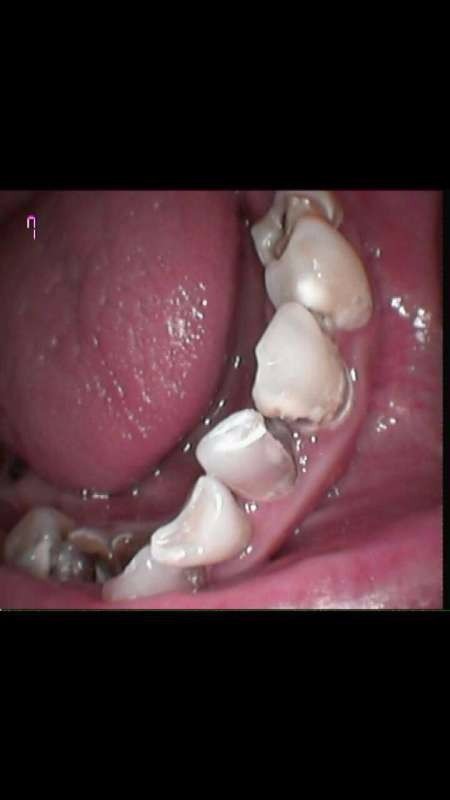

患者男25岁,右下23之间34之间45之间,邻面龋深答髓腔。冷热刺激痛。根管治疗后烤瓷牙修复